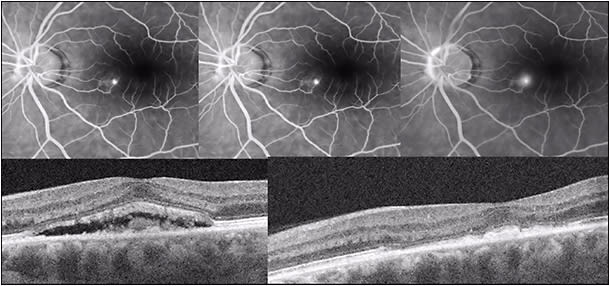

The natural history in the vast majority of CSC cases is spontaneous resolution within 2-3 months (so-called classic CSC). In these cases, central vision is minimally affected and usually returns to normal after reabsorption of the subretinal fluid (Figure 1). However, as many as 10% of all patients with CSC develop persistent serous macular detachment (chronic CSC or “diffuse retinal pigment epitheliopathy” [DRPE], lasting 3 months to 6 months or longer).10 In these DRPE cases, progressive and irreversible visual decline can be associated with the development of central RPE atrophy and (due to increased diffusion distance between the oxygenating and nourishing choriocapillaris, trophic RPE, and the photoreceptors) cystoid macular degeneration and foveal atrophy (Figures 2 and 3).11-15